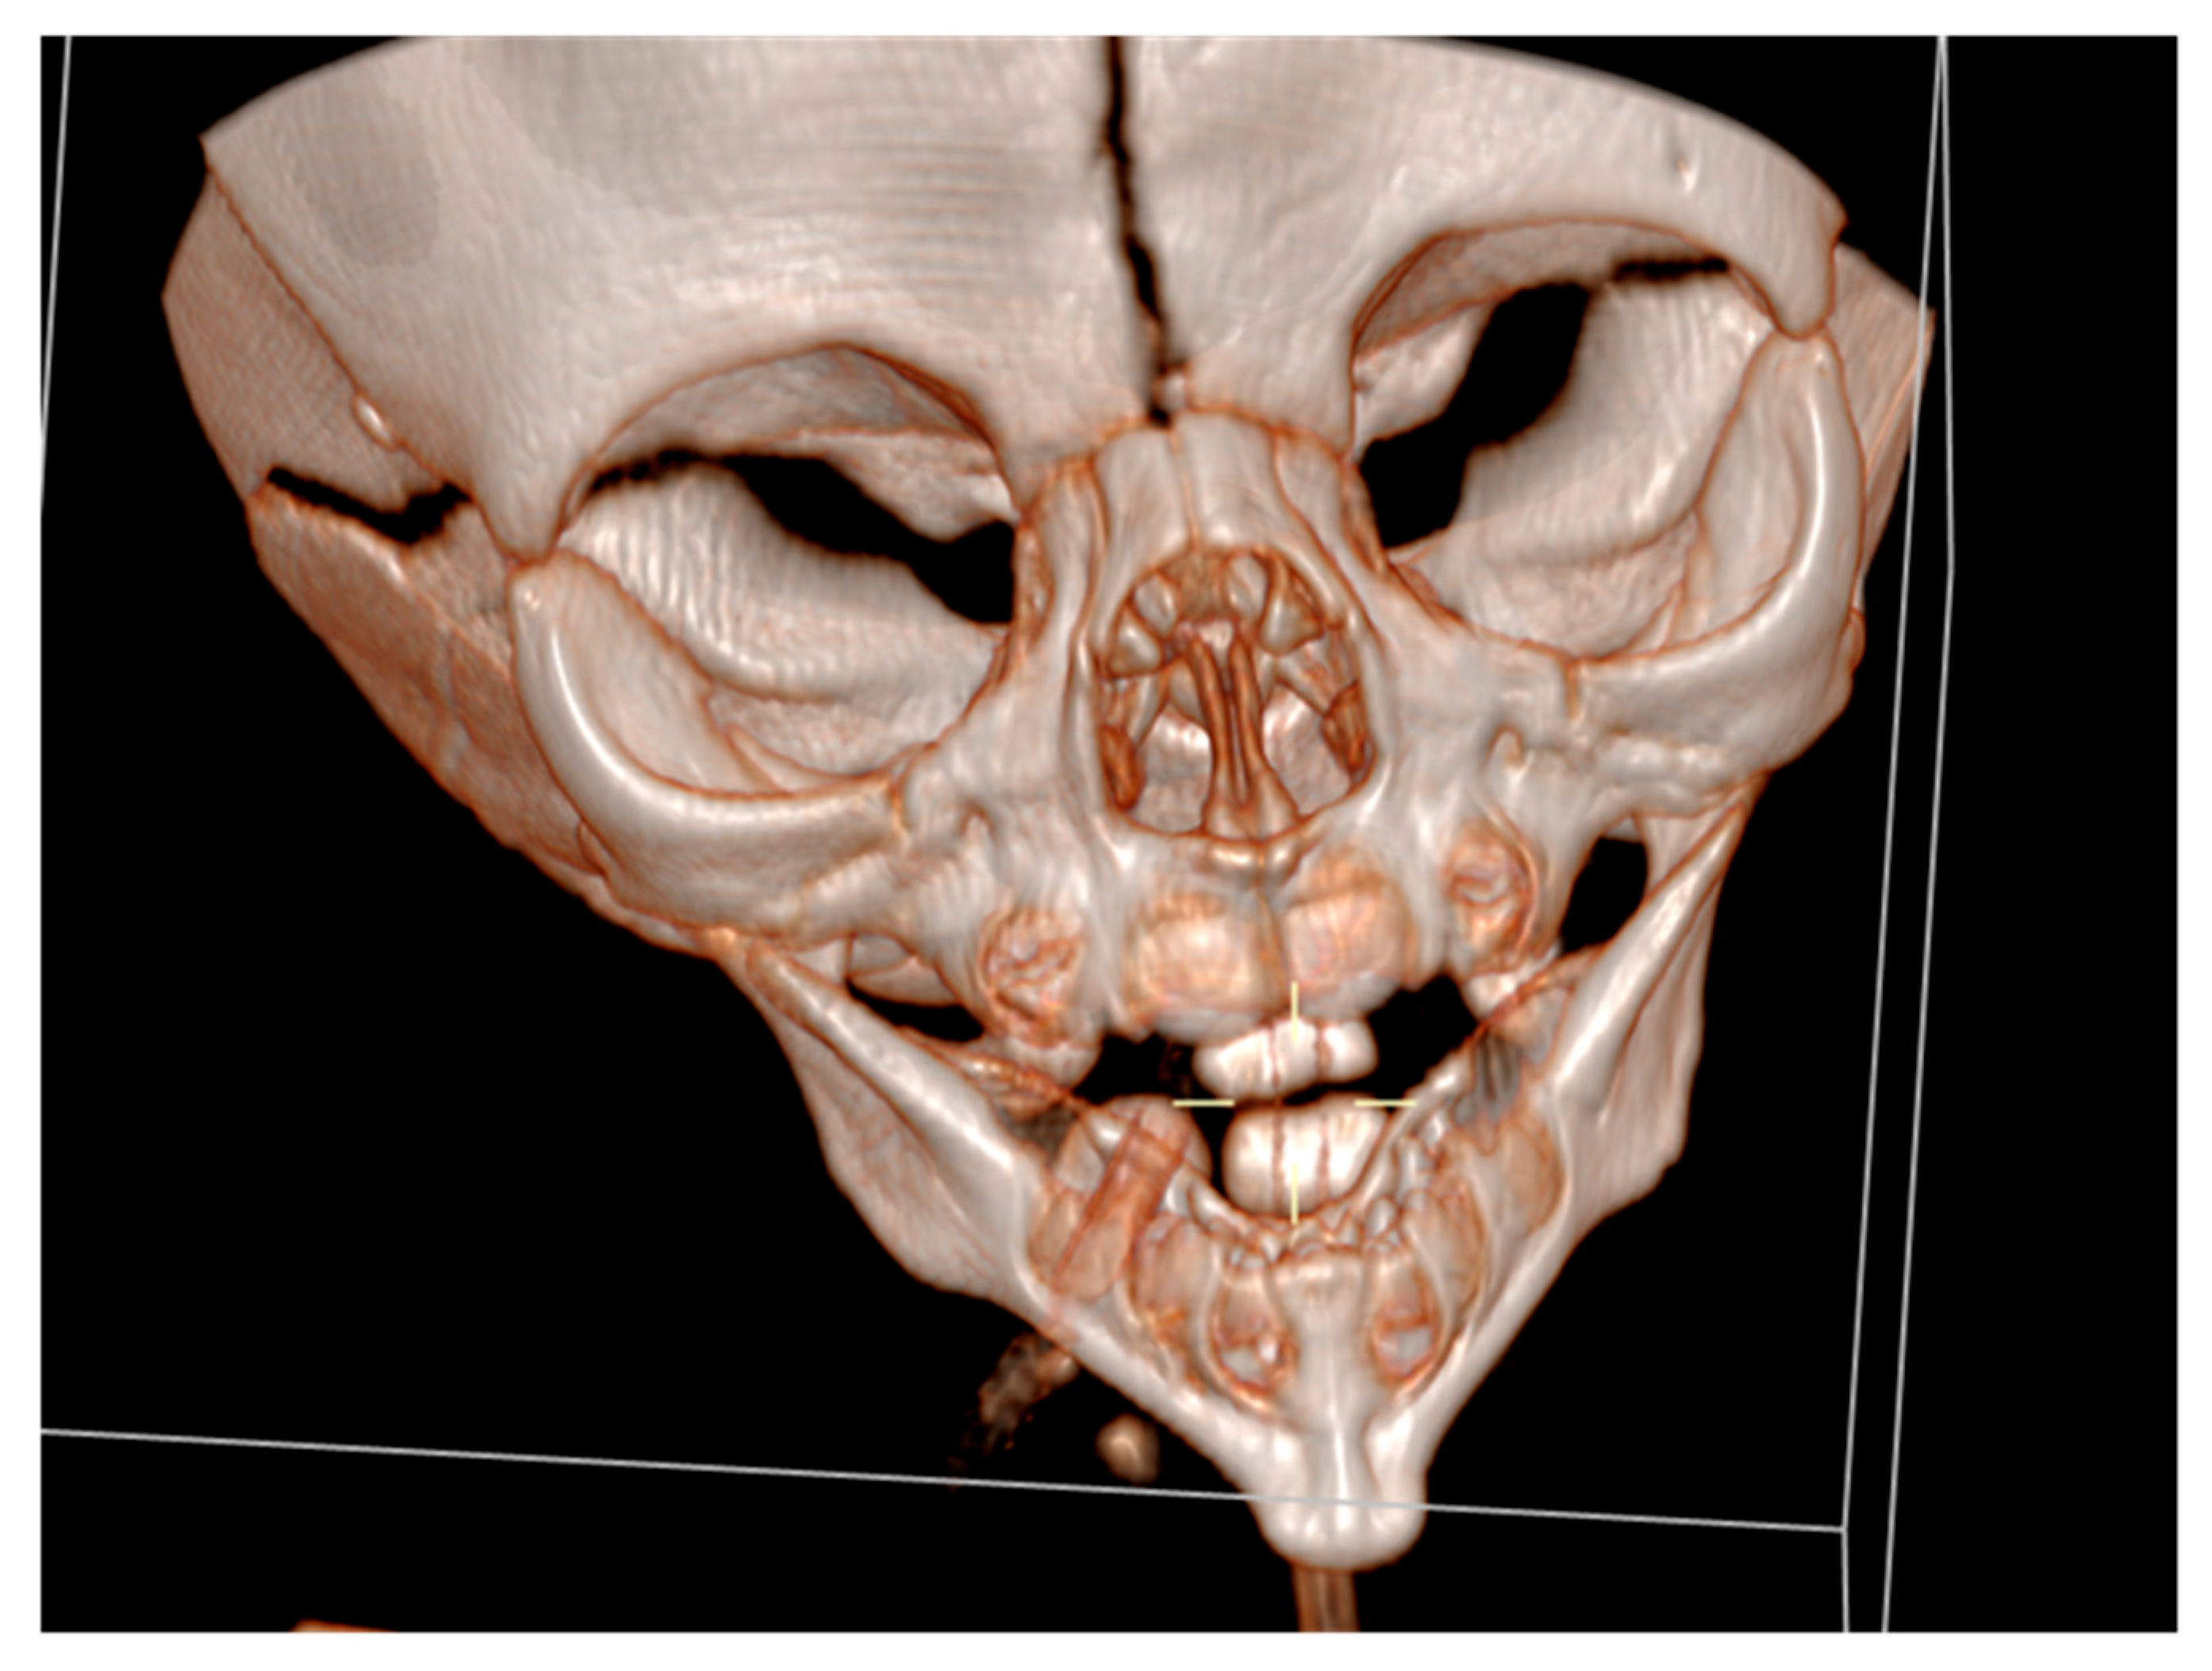

Mandibular hypoplasia, hypoglossia, and high-arched palate were evident upon delivery. There was a significant retrognathia, and the anterior two-thirds of the tongue were missing. The posterior third of the tongue was present, and it was bud-shaped and barely motile. This case is depicted in Figure 1. Due to the severity of these malformations, breastfeeding and bottle feeding were not possible. A nasogastric tube was inserted. The newborn was otherwise in good physical condition, and she had no breathing problems. Apgar score was 9 at the 1st, 5th, and 10th minute, respectively, and all vital signs were normal. Physical examination findings also included low-set ears, hypertelorism, broad nasal bridge, and a prolonged and smooth philtrum. Ear canal and tympanic membrane appeared normal on both sides. Hands and feet were normal. There were no other musculoskeletal deformities. During auscultation, heartbeats were mainly heard on the right hemithorax. Chest X-ray and echocardiogram confirmed that there is mirror-image dextrocardia.

Cranial ultrasound showed no pathological findings, except for discretely hyperechoic periventricular white matter. A computed tomography of the facial region described the mandibula as hypoplastic and narrow (Figure 3).

It had underdeveloped body region and pointed chin. Only three tooth germs of the lower frontal teeth were present, specifically one lower medial incisor and two lateral incisors. Temporomandibular joints were normal (Figure 4).

Figure 1. Newborn with hypoglossia and micrognathia without ear anomalies.

Figure 3. A computed tomography of a narrow and hypoplastic mandibula.